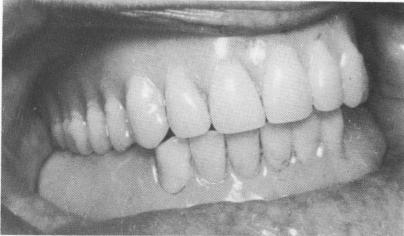

Fig. 12-30. With clean and proper sugery, healing takes place uneventfully. Notice the tissue around the implant posts as they appeared 12 years postoperatively.

Although Metz's approach and those of some other operators are useful, Linkow believes that clean, aseptic, and intelligent surgery over the original in-

cision causes a minimum amount of trauma and healing is quite good (Fig. 12-30) .

1 Tissue around dental implant posts 12 years postoperatively